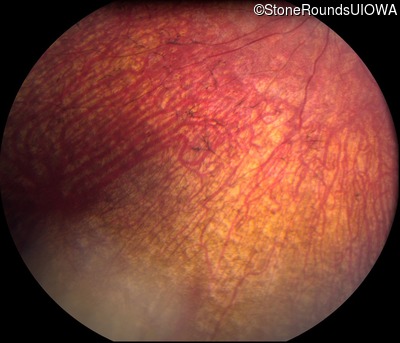

Fundus Photography - Right - Hand Motion sc

Exemplar